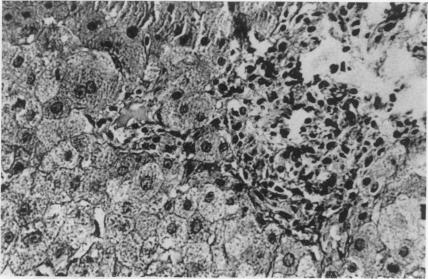

Cholestatic jaundice associated with chills, pruritus and blood eosinophilia developed in a patient who received prajmalium bitartrate therapy for ventricular arrhythmia following acute myocardial infarction. Discontinuation of the drug resulted in a spontaneous improvement in the clinical and biochemical findings. Challenge by prajmalium bitartrate caused rapid reappearance of the clinical and biochemical features. In immunological studies, deposits of IgG and IgA were detected at the bile canaliculi by fluorescent staining, and the patient's lymphocytes produced macrophage migration inhibition after in vitro incubation with prajmalium bitartrate. Thus, laboratory results support the assumption of an allergic mechanism.

一名急性心肌梗死后接受双异丙吡胺治疗室性心律失常的患者出现了伴有寒战、瘙痒和血液嗜酸性粒细胞增多的胆汁淤积性黄疸。停用该药物后,临床和生化检查结果出现自发改善。再次使用双异丙吡胺后,临床和生化特征迅速重现。在免疫学研究中,通过荧光染色在胆小管处检测到IgG和IgA沉积,并且患者的淋巴细胞在与双异丙吡胺进行体外孵育后产生巨噬细胞游走抑制。因此,实验室结果支持过敏机制的假设。